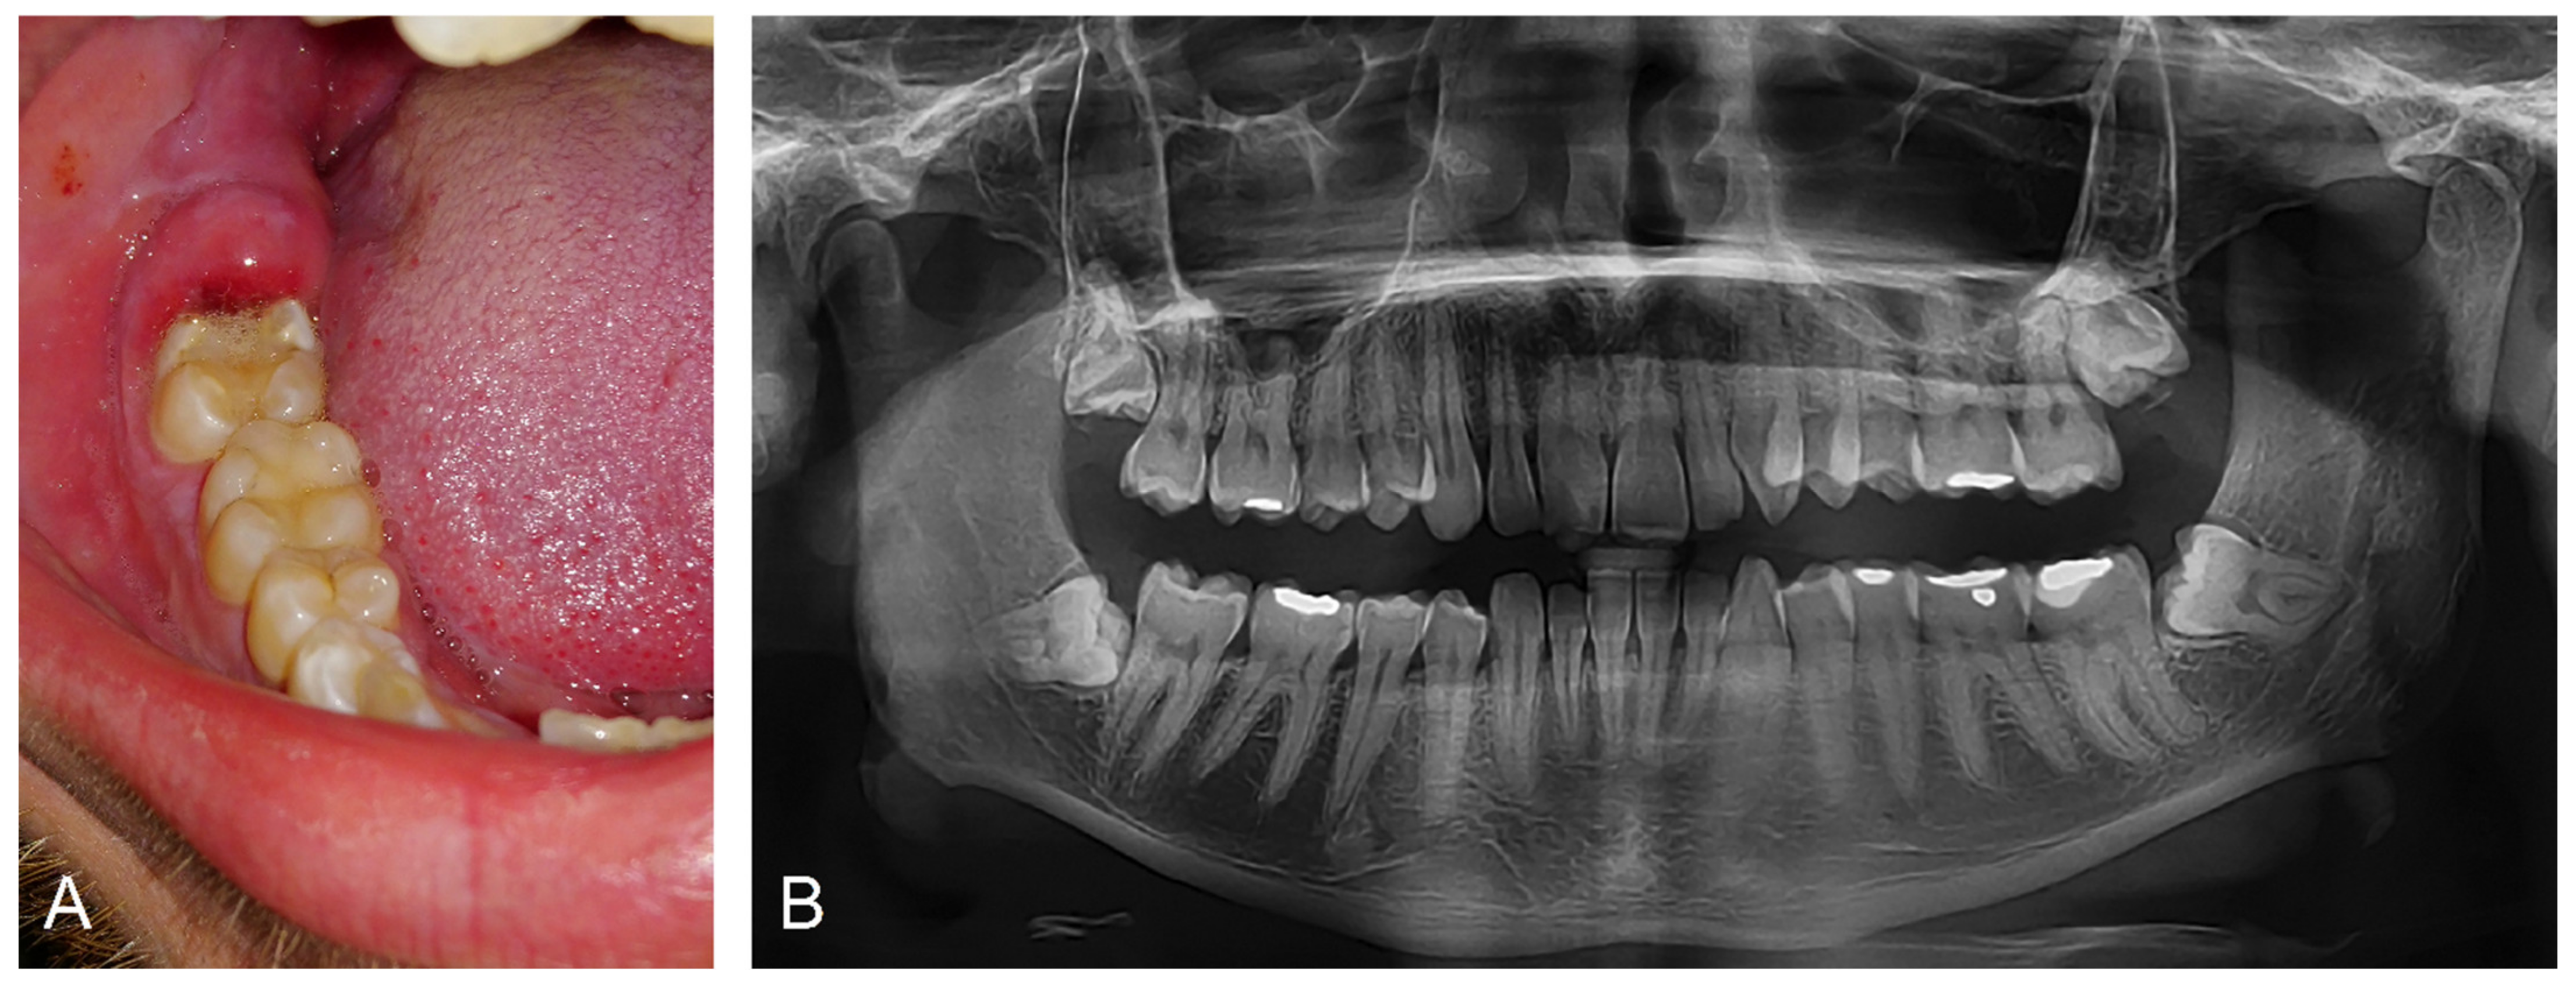

2.4. Clinical Manifestation and Diagnosis